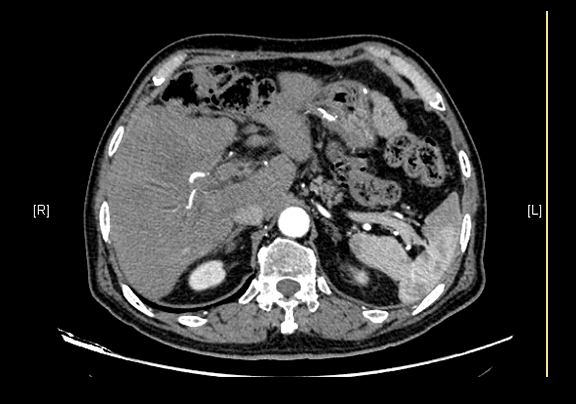

下腹部增强CT示:肝右前叶胆管细胞癌并胆管扩张可能性大。

通过调节窗宽窗位调整CT序号,对肿瘤,肝实质,胆囊,下腔静脉,肿瘤,肝动脉、门静脉及肝静脉等进行三维重建;系统自动计算肿瘤体积和肝脏体积。(图2—截图1---后链接截图2)

模拟手术操作,自动计算切除肿瘤体积。肝脏体积为1324ml,肿瘤体积为286.1ml,肿瘤体积为肝脏体积的21.6%,通过比对70-80岁正常肝脏体积为1118.08±190.14ml,通过术前模拟手术,精准判断切除后剩余肝脏体积能耐受,避免肝衰竭发生。术前手术方案的规划。

麻醉成功后,病人平卧位,常规碘伏消毒手术区皮肤,铺无菌巾、单。取右肋缘下切口,分层入腹,纱布垫护皮,上框架拉钩。探查见:腹腔粘连严重,肝脏质地及形态可,右肝Ⅴ、Ⅵ段交界处,可触及直径8cm不规则肿块。既往胰十二指肠切除术手术史,仔细分离腹腔粘连,游离右半肝,肿瘤未侵犯胆肠吻合口,决定保留吻合口,行姑息性肝癌肝部分切除术。游离肝脏与周围组织粘连,沿肿瘤边缘约1cm,依次钳夹、切断、结扎肝断面各结构,切除肿瘤及部分肝组织。断面渗血处分别缝扎止血,填塞止血敷料后,将创面对拢缝合。温蒸馏水3000ml冲洗腹腔,止血,于肝断面旁放置引流管1根于右侧腹壁穿孔引出。清点纱布器械无误,分层缝合腹壁切口。术中出血约500ml,未输血。术后血压120/65mmHg,术后病人安返病房。手术顺利,麻醉满意,解剖标本,肿块直径约8cm,灰白色,家属过目后送病理检查。结果回示:(肝右叶)低分化腺癌。手术时手术者可开启Hisense CAS系统手势控制功能,对肿瘤的解剖结构进行实时、全方观察、评估,起到术中导航作用。

(肝右叶)低分化腺癌,结合形态学及免疫组化结果,意见为低分化胆管细胞癌,肿瘤于肝内弥漫分布(大者范围7*4),累及局部肝被膜,神经侵犯(+),紧邻肝断端,部分区域似累及手术切缘(请结合术中所见综合评价);周边肝组织萎缩伴肝细胞轻度水肿、淤胆,汇管区纤维增生伴慢性炎细胞浸润。

随访1月,符合肝术后改变,右上腹腔团片状液气混杂密度影,胃术后所见,腹腔积液。